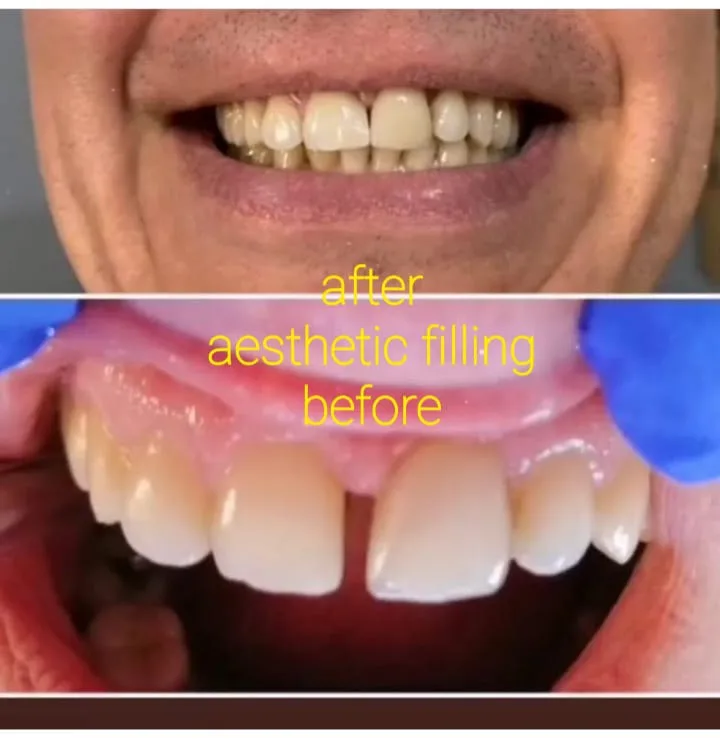

✅ Esteettinen hammaslääketiede: valkaisu ja restaurointi.